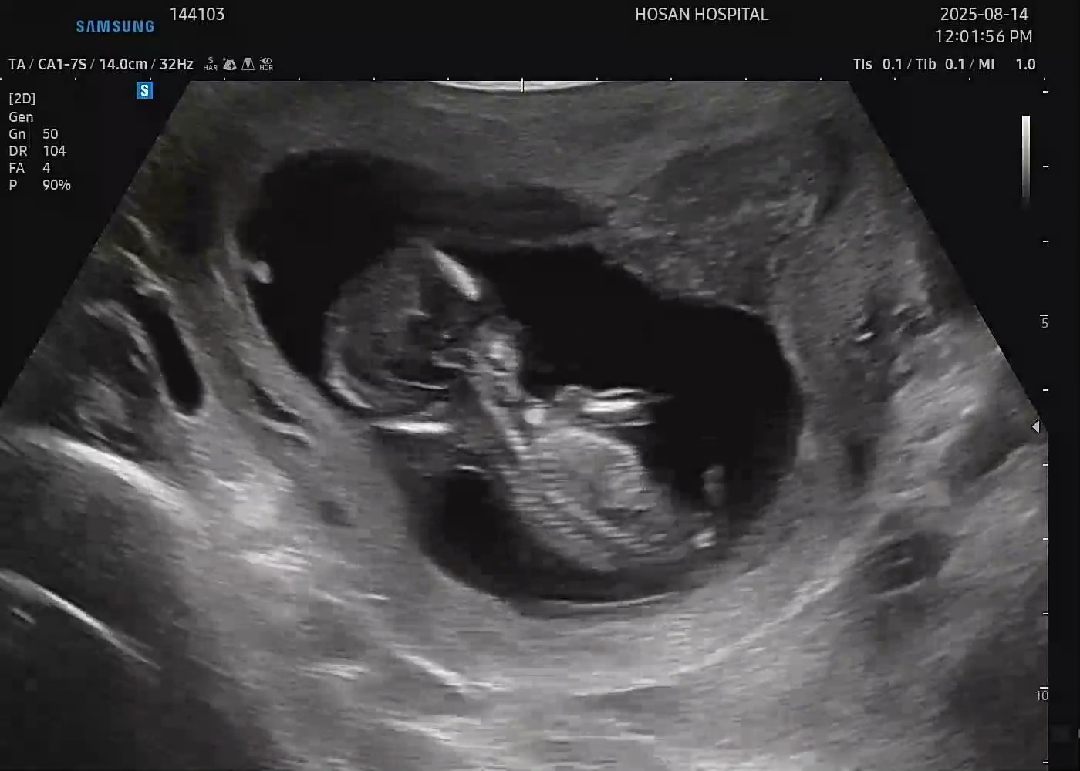

13주차 초보맘 각도법 고수님들 부탁드립니다!!

초음파가 너무 흐릿..하긴한데 각도법 고수님들의 판단을 부탁드려봅니다🤯🙏

딸같아요